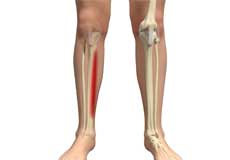

Shin Splints

Shin splints are pain and inflammation of the tendons, muscles and bone tissue along the tibia or shinbone (lower leg). It occurs because of vigorous physical activities such as exercise or sports. The condition is also referred to as medial tibial stress syndrome (MTSS).

Fractures of the Tibia

The lower leg is made up of two long bones called the tibia and fibula that extend between the knee and ankle. The tibia or shinbone is the larger of the two bones. It bears most of the body’s weight and helps form the ankle joint and knee joint. A crack or break in the tibia is referred to as a tibial fracture.